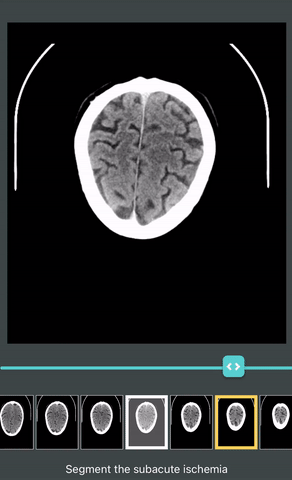

Ischemia segmentation

Here you see a single target image highlighted (the user is prompted to segment the ischemia on only that image), but the entire series is displayed for context. Each image here would be represented in a single row in the CSV.